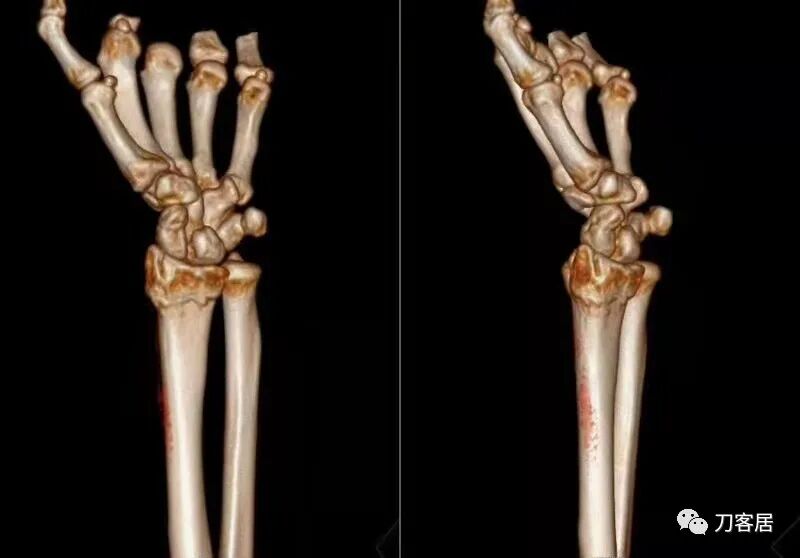

下面是这个6岁孩子,尺桡骨远端双骨折的术前及术后片子和外观照片。

2.  这个骨折处理起来也很简单,单纯的打石膏托或者中医的小夹板,或者正规的包括腕关节和肘关节的管型石膏外固定4周即可治愈该骨折。实在不行,如果这个孩子比较听话,不太调皮的话,用一本书,一个三角巾悬吊固定4周,都可以治愈该骨折。但是给这个患者用外固定架做了手术,而且桡骨远端的几颗克氏针距离骨折线太近,其中一枚克氏针进入到骨折间隙内。从这个术中图片来看,术者的外固定手术技术也有待于进一步的提高。毕竟术者应该还很年轻。从X线片来看,前臂及手的尺侧有不透光影,应该还使用了外固定石膏绷带托,而且我猜测应该是高分子的石膏绷带托,这个是纯属猜测,不一定是对的,不过如何解释前臂尺侧的不透光影呢?如果真是用了石膏绷带外固定的话,那为啥要做手术呢?外固定架术后就不该再用石膏绷带托辅助了。

这个病例,6岁的孩子,尺桡骨骨折在同一个平面,且都为小斜行骨折,不是螺旋形,不是粉碎性,不是成角移位性,属于稳定性尺桡骨双骨折,根本就没有任何手术的适应症。